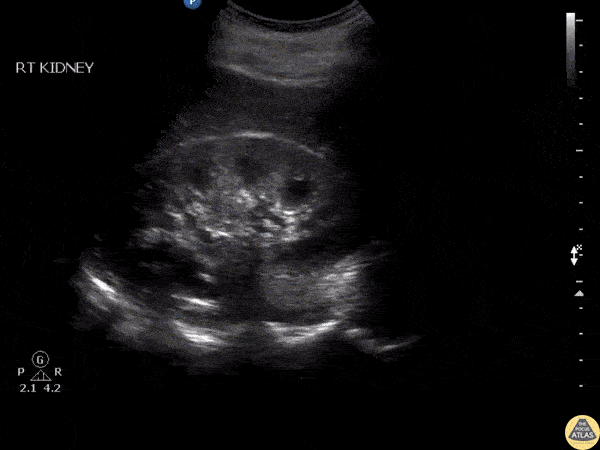

Renal/GU - Medullary Pyramids

A patient was being evaluated for flank pain. This clip shows findings of normal but prominent medullary pyramids as indicated by how they taper down toward the renal pelvis. Image courtesy of Robert Jones DO, FACEP @RJonesSonoEM Director, Emergency Ultrasound; MetroHealth Medical Center; Professor, Case Western Reserve Medical School, Cleveland, OH View his original post here